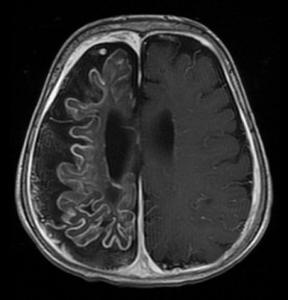

头颅平片一般正常,不过,垂体明显增大的病人头颅平片也可有蝶鞍增大的表现,CT和MRI对诊断有重要的意义,本病垂体CT和MRI的表现有:垂体增大或垂体占位(可伴鞍上扩展),垂体柄增粗,空鞍,垂体有囊性病变,垂体增大或垂体占位是最常见的影像学改变,约见于90%的病人,鞍上扩展亦相当常见(见于60%~70%的病人),本病垂体多呈弥漫性增大,这一点与垂体腺瘤不同,对鉴别诊断有一定的意义,垂体柄增粗则较少见,多发生于神经垂体和漏斗受累的病人,空鞍和垂体囊性病变则更为少见,久病者可有垂体萎缩但蝶鞍仍扩大,少数病人垂体CT和MRI检查可无异常发现。